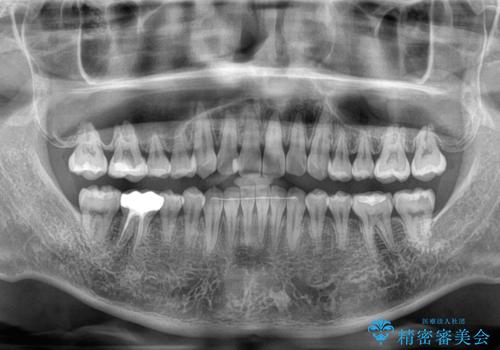

- 上下前歯のデコボコと突出感を気にして来院された患者様です。

目立たない装置を希望されたため、インビザラインによるマウスピース矯正を行うこととしました。

矯正治療後に銀歯をセラミックに替えたいとの要望があり、概ね歯列が整ったところで銀歯をセラミックに替え、仕上げにインビザライン1セットを使用して最終的に歯列を整えました。